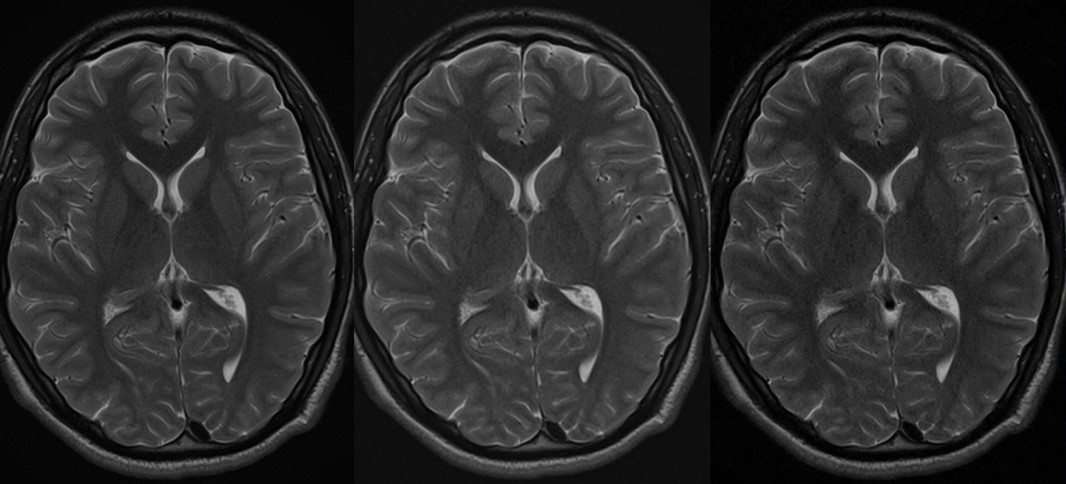

Original

Compressed SPEEDER 2.0

Compressed SPEEDER 2.5

Время сканирования 3:10

Vantage Orian 1.5T

Время сканирования 1:46

Время сканирования 1:18